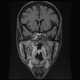

Radiation-induced optic neuropathy